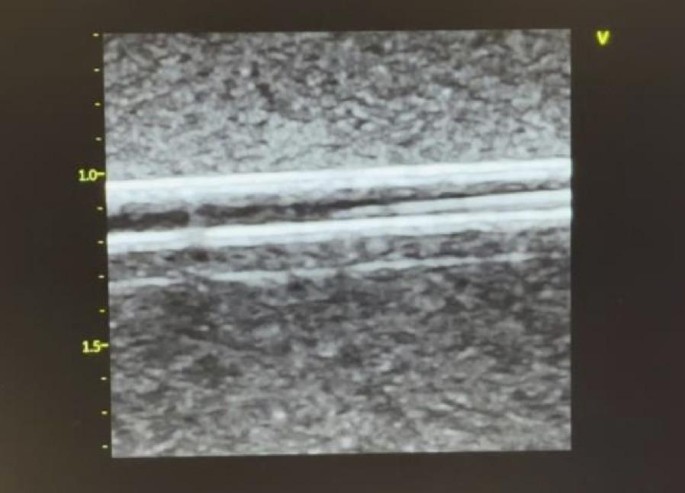

After placing water-based ultrasound jelly on the cannulation phantom, the operator placed a linear array probe (8-18 MHz GE, Vivid S70N, Bedfordshire, UK) held in the non-dominant hand to obtain optimal short axis (cross-sectional, out of plane view) and long axis (longitudinal, in plane) views of the vessel. Using the dominant hand, a 22G needle with a length of 40 mm was inserted at an angle of about 30–45 degrees, at a point 5–10 mm proximal to the middle marker of the probe on to the surface of the phantom, while keeping an optimal cross-sectional view. The needle was inserted until it reached the anterior wall of the vessel. The needle was then cautiously advanced at a shallower angle with ultrasound imaging of the indentation and penetration of the anterior wall of the vessel. The puncture of the vessel was also felt by the operator mimicking what one may expect in clinical practice. Extreme care was taken to ensure that the tip of the needle was maintained in the middle of the vessel lumen giving the appearance of a bullseye while gradually advancing the needle and the probe in short < 1 mm increments. This was to ensure that the needle did not breach the posterior vessel wall and the entire length of the needle tip was inserted. Once the needle was confirmed to be in the centre of the vessel lumen using US, a metal guidewire was inserted through the needle for insertion of a PICC using a Seldinger technique (Figs. 3 and 4). A metal guidewire was used as it could easily go through the caliber of the needle that was used and could readily be visualized using US. Non-ultrasound confirmation of the correct placement was also achieved by continued advancement of the guide wire which resulted in the guide wire being physically visible at the exit end of the vessel outside the phantom.

Ultrasound imaging demonstrating the longitudinal (in plane) view of the vessel with the guide wire seen within the vessel lumen.